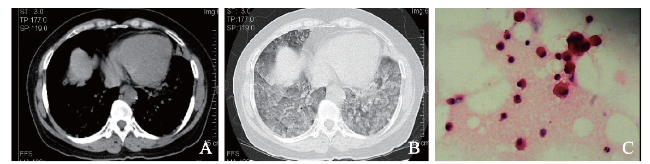

例1 患者女,66岁。因反复咳嗽3月余、加重伴少量咳白痰1个月于2014年4月20日收入我科。患者3个月前受凉后反复咳嗽,未予重视,近1个月来加重并伴咳白痰,无发热,有乏力,睡眠差,起病以来体质量下降约5 kg。既往史及个人史无特殊。入院体格检查:体温36.8 ℃,脉搏90次/分,呼吸20次/分,血压120/70 mm Hg(1 mm Hg=0.133 kPa)。生命体征平稳,双肺呼吸音清,可闻及Velcro啰音。入院后完善检查,血常规:血红蛋白132 g/L,白细胞5.51×109/L,嗜酸性粒细胞0.13×109/L,血小板251×109/L。肿瘤标志物癌胚抗原6.9 μg/L,细胞角蛋白19片段测定、神经元特异性烯醇化酶测定、甲胎蛋白等均未见明显异常,免疫标志物均未见异常。予头孢哌酮钠-舒巴坦钠3.0 g、每日2次,莫西沙星0.4 g/d,哌拉西林钠-他唑巴坦钠4.5 g、每日2次静脉滴注,患者症状无好转。4月24日完善纤维支气管镜(纤支镜)检查,送BAL病理检查见活动性鞭虫,住院期间经甲硝唑0.5 g每日2次联合复方磺胺甲恶唑0.8 g每日3次抗鞭虫治疗后症状好转。4月29日CT示双肺可见弥漫斑片状密度增高影,边缘模糊、密度不均,部分融合成片,大部分为磨玻璃样密度,呈地图状改变,内见空气支气管征(图1A、B)。因双肺弥漫渗出性病变,考虑为肺泡蛋白沉积症可能性大。5月5日BAL苏木素-伊红(HE)染色示大量泡沫样细胞(图1C)、组织细胞,少量纤毛柱状上皮细胞、淋巴细胞、中性粒细胞及少量散在退变核异质细胞,个别异常核分裂;过碘酸雪夫(PAS)染色(-)。病理活组织检查(活检)(左舌叶和下叶肺组织)送检组织3微粒:镜下为少许肺组织,部分区域肺泡上皮增生,腺体排列较密集,细胞核浆比例失调,核增大,可见核仁,呈轻 ~ 中度非典型,核分裂未见;免疫组织化学染色(免疫组化)示癌胚抗原(±),Ki-67 < 5%,CK7(+);PAS示肺泡上皮内、间局灶红染物沉积,六胺银(-),抗酸(-)。考虑为肺泡上皮增生丰富活跃,不排除贴壁生长低级别肺腺癌。患者经吸氧、抗感染、平喘、祛痰等治疗症状有所好转后即自动出院,家属未同意进一步肿瘤相关治疗,未再复诊。

图1 例1肺腺癌合并鞭虫感染患者的胸部CT及BAL涂片结果

A:胸部CT纵隔窗;B:胸部CT肺窗;C:BAL涂片(HE染色,×400)